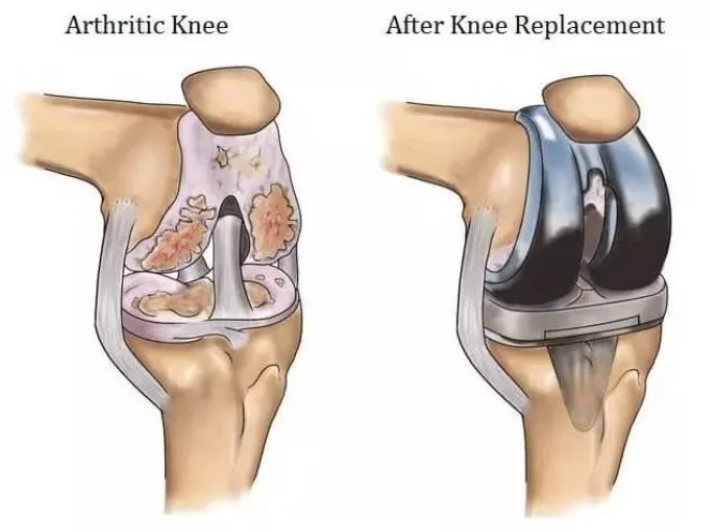

In simple terms, a knee replacement is a surgery performed to replace the original knee with an artificial joint. The implants are made of a combination of ceramic, metal and plastic materials.Usually, people suffering from osteoarthritis, arthritis, rheumatoid arthritis, developmental abnormalities, bone death, accidents or obesity are recommended such surgeries because it affects their daily life and mobility.

A total or partial knee replacement surgery can be performed depending on the condition of the patient. While performing a total knee replacement surgery, the bones in the femur, tibia and patella are resurfaced. A plastic cushion is often used to replace the cartilage between the tibia and femur bones.

Osteoarthritis is one of the primary reasons for knee replacement. To postpone the surgery patients should take care of the following: